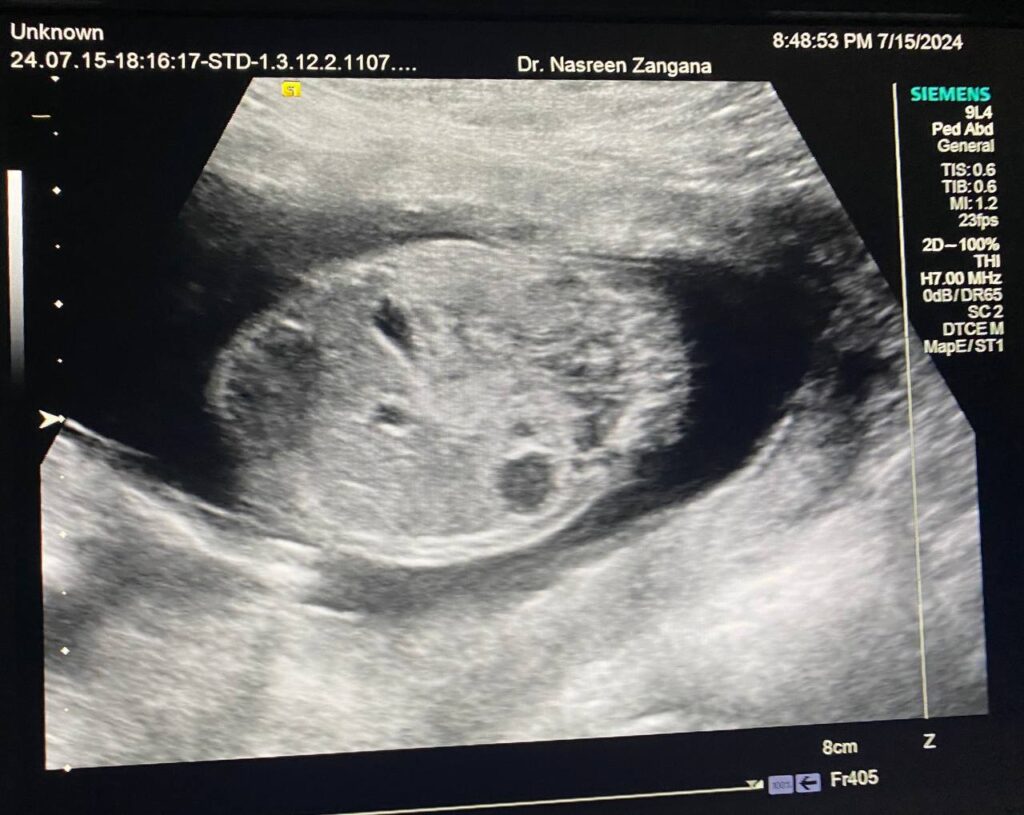

Fetus , right kidney Polycystic?

When 14-15 weeks